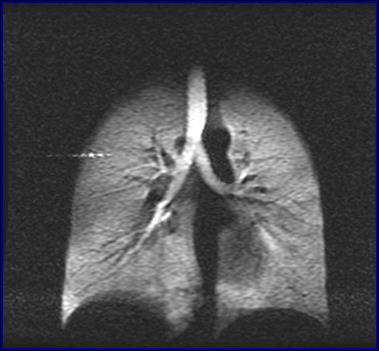

中国科学院武汉物理与数学研究所研究员周欣、中科院院士叶朝辉带领的科研团队克服技术难关,研制出具有自主知识产权的人体肺部气体磁共振成像系统。该系统弥补了传统磁共振成像不能检测肺部空腔结构的缺陷,成功“点亮”人体肺部,且能同时获得肺部气气、气血交换的功能信息,成为肺癌等重大疾病早期科学研究和诊断的新利器。目前,该成果已转移转化成立产业化公司,且正在申请医疗器械注册证。2018年7月在同济医院建立了第一个肺部气体磁共振临床检测中心,用于大规模临床病例获取工作。

人体肺部气体磁共振成像系统

左:核心装置超极化气体发生器 右:我国首幅人体肺部气体磁共振成像图